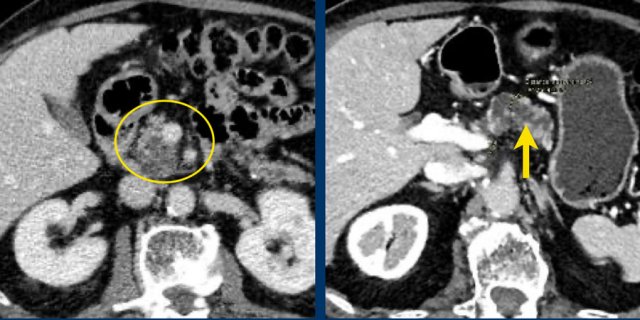

Another branch-duct IPMN found on screening with two nodules (circle and arrow).

T1W-images with fatsat before (left image) and after contrast (right image).

EUS with contrast agent revealed 2 foci without enhancement most likely mucus plugs.

6 years later the cyst was unchanged.

75 year old male with a 2.7 cm side branch IPMN in the pancreatic head (circle).

During follow up one year later dilatation of pancreatic duct was seen.

EUS showed a resectable adenocarcinoma.